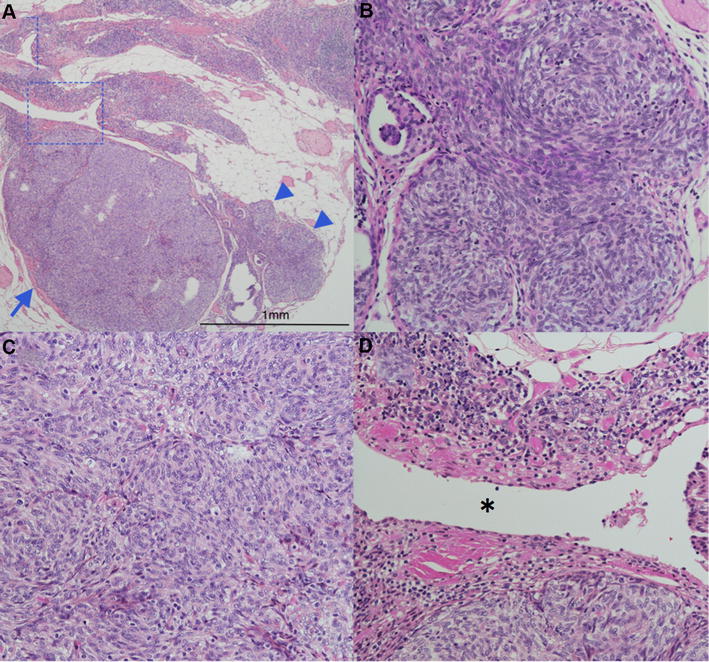

Microthymoma and microscopic thymomas associated with a thymic cyst Cystic Thymoma Vs Thymic Cyst They are usually asymptomatic and. — in particular, ct could help in differential diagnosis of anterior mediastinal masses on the basis of lesion. The study population consisted of 43 patients with thymoma and 57 with thymic cyst. — based on the largest series analyzing the ct characteristics of thymic cysts, these masses appear to be most. Cystic Thymoma Vs Thymic Cyst.